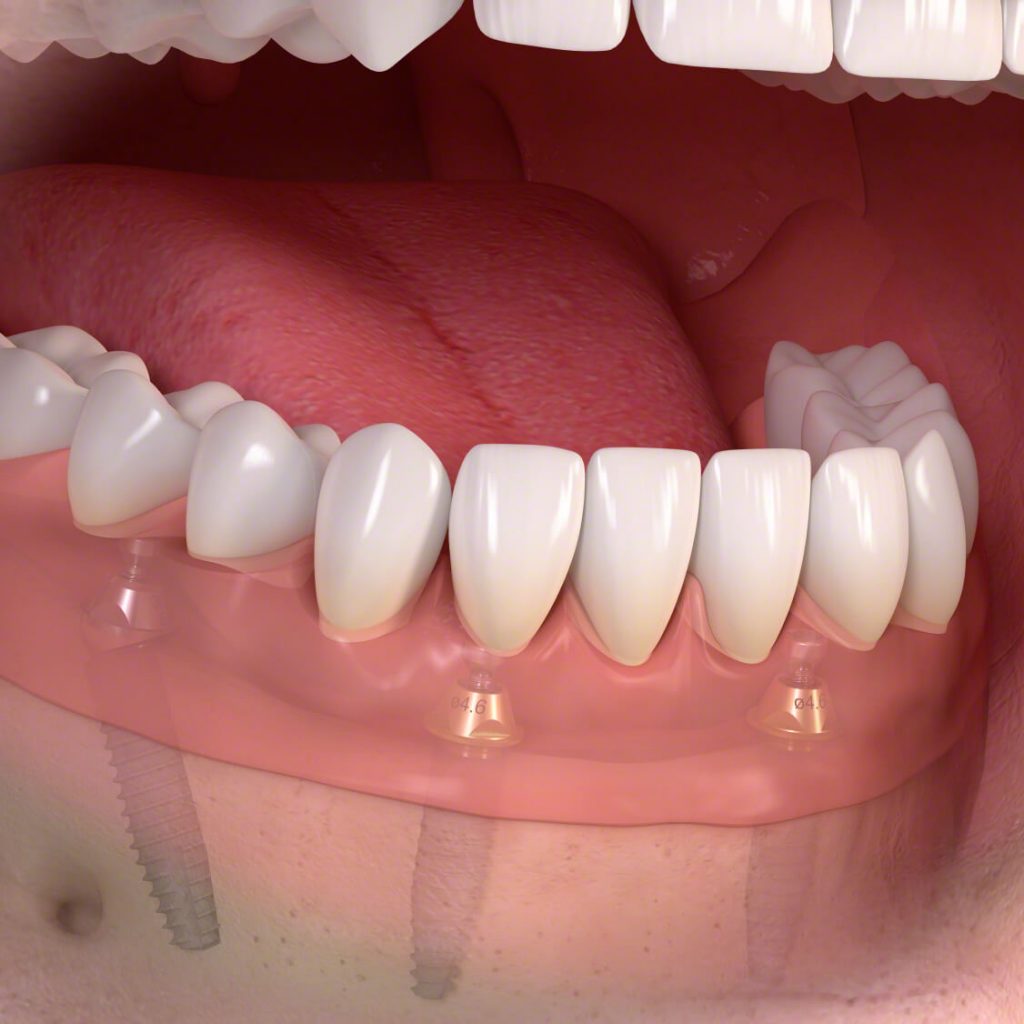

5.) Implantátum fej behelyezése Az optimális lágyrészviszonyok elérése után eltávolítjuk az ínyformázó csavart, majd kiválasztjuk a megfelelő implantátum fejet és becsavarjuk azt a fog implantátumba. Az fogászati implantátum fej lehet gyárilag előre legyártott, azonban készülhet egyénileg is.

6.) Precíziós lenyomatvétel és tervezés Az implantátumfejek behelyezését követő lépés a lenyomatvétel. Ekkor lényegében a fogívekről készítünk egy másolatot, amire a fogtechnikai laboratóriumnak szüksége van a pótlás elkészítésére.

7.) Fogpótlás, korona készítése Az implantációs fogpótlások készítésére szakosodott kollégáink elkészítik a szájviszonyoknak megfelelő legoptimálisabb és legesztétikusabb pótlást. Fogpótlás egyéntől és szituációtól függően lehet korona, híd, de akár kivehető pótlás is. Teljes fogsor beültetésénél szintén esettől függően lehet rögzített híd vagy kivehető pótlás.

8.) Vázpróbák A laboratóriumból megkapott, de még félkész munkát bepróbáljuk, hogy az biztosan pontosan illeszkedjék az implantátumra.

- Hogyan kell elképzelni a fogászati implantátumot? – A ma használt fogászati implantátumot legegyszerűbben egy csavaros fogként tudjuk elképzelni. Anyaga titán, melyet a szervezet tökéletesen befogad, abból semmilyen káros reakciót nem vált ki. A műtéti úton beültetett műgyökerekre egy implantátum fej kerül, ami a fogpótlásokat (korona, híd, kivehető pótlás) tartja.

- Hasonlóan fogok tudni rágni az implantátumokkal?– Igen. Az implantátumokba csavarozott ún. fejekre helyezett koronák, hidak, de a kivehető pótlások is képesek az eredeti esztétikát és a funkciót is helyreállítani.

Természetesen van lehetőség teljes fogsor beültetésre is. Teljes fogsor implantáció esetén a legjobb esztétika elérése véget az implantátumok rögzíthetnek hídpótlást vagy kivehető pótlást is. Utóbbi esetben jóval nagyobb stabilitás és komfort érhető el, mint a hagyományos teljes lemezes pótlásokkal.